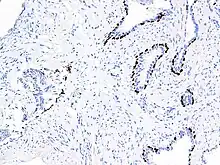

p63 staining on prostate cancer tissue using antibody clone IHC063

Main staining patterns on chromogenic immunohistochemistry.

p63 immunostaining has utility for head and neck squamous cell carcinomas, differentiating prostatic adenocarcinoma (the most common type of prostate cancer) and benign prostatic tissue;[23] the nuclei of the basal cells of normal prostatic glands stain with p63, while the malignant glands in prostatic adenocarcinoma (which lacks these cells) do not.[24] P63 is also helpful in distinguishing poorly differentiated squamous cell carcinoma from small cell carcinoma or adenocarcinoma. P63 should be strongly stained in poorly differentiated squamous cell, but negative in small cell or adenocarcinoma.[25]

Cytoplasmic staining on immunohistochemistry is seen in cells with muscle differentiation.[26]